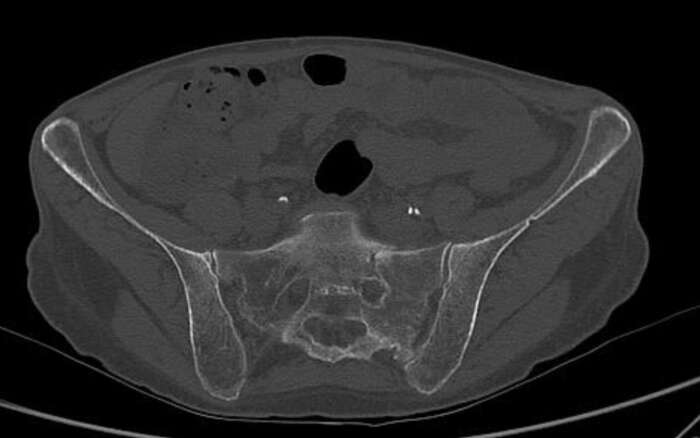

In diesem Beispiel war die Patientin vier Wochen nach einem Sturz nur noch mit Krücken und mit Schmerzen mobil. Die Computer Tomographie (CT) zeigte einen nicht verschobenen Bruch des Kreuzbeins und eine leicht verschobene Fraktur des Schambeins. Während der Operation implantierten wir CT-gesteuert zwei 7,3-mm-Schrauben. Die Schrauben gingen durch beide Ilio-Sakralgelenke und erste und zweite sakrale Wirbelkörper. Die Patientin konnte am nächsten Tag nach Hause entlassen werden und war schmerzfrei mobil.

Fraktur der linken Seite des Sakrums auf Höhe von S1

Fraktur huefte 1